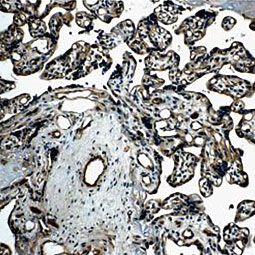

![TIE2 antibody [21G7] (GTX52471)](/upload/media/research/Cancer/Angiogenesis/6.jpg)